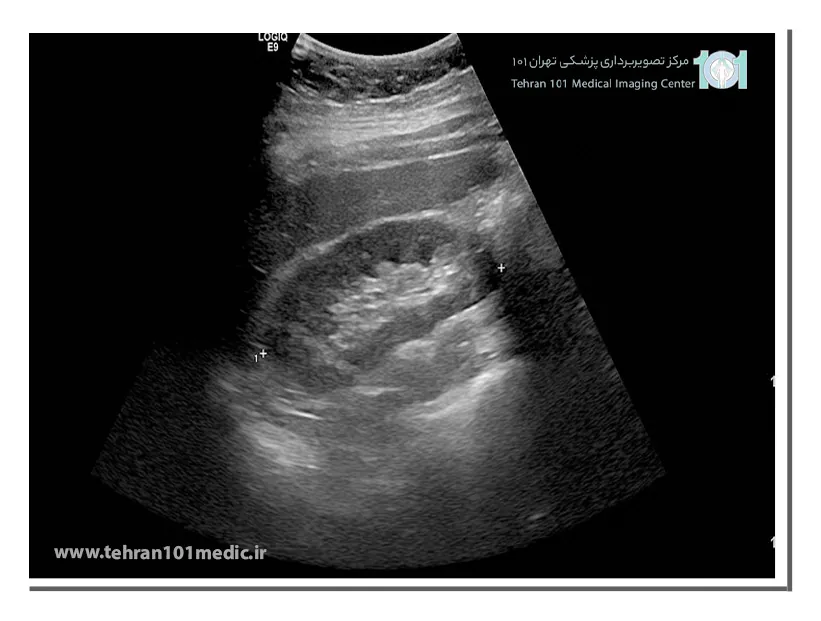

سونوگرافی کلیه از امواج فراصوت با فرکانس بالا برای تهیه تصاویر از درون کلیهها استفاده میکند. در طول اسکن امواج صوتی به ناحیه کلیه ارسال شده و تصاویر سیاه و سفید بر روی صفحه مانیتور دیده میشود. توسط سونوگرافی اندازه، موقعیت، شکل و ساختارهای کلیه و اطراف آن مانند مثانه و حالب تشخیص داده میشود.

با ورود امواج فراصوتی به بدن، تصاویری از بافت کلیه روی مانتیور نشان داده که با لغزاندن پروب، ناحیه مورد نظر از جهات مختلف مورد بررسی قرار میگیرد. سونوگرافی کلیه یکی از بهترین روشها برای بررسی سلامت و چگونگی عملکرد این عضو حیاتی از بدن بوده که ممکن است پزشک درخواست انجام آن به تنهایی یا در کنار آزمایشها را داشته باشد. در سونوگرافی از امواج صوتی با فرکانس بالا استفاده میشود که در محدوده شنوایی انسان قرار ندارد.